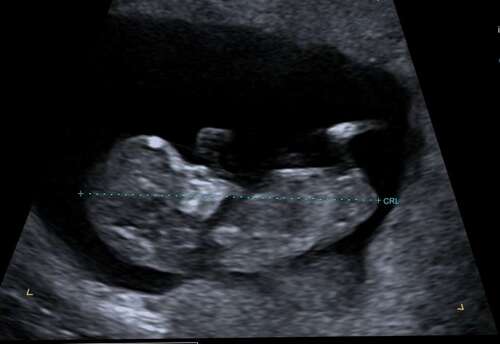

Is hier nog iets op te zien misschien 鈽猴笍? 13 + 1

En heb deze nog 馃き